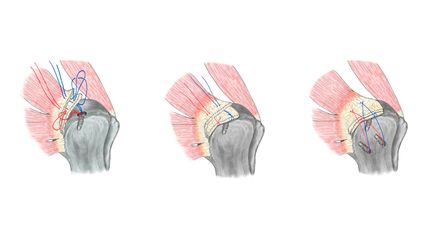

Zusammenfassung der OP-Technik

An unserer Klinik erfolgt bei B2-Frakturen in der Regel die plattenosteosynthetische Versorgung mit folgender Technik (siehe Abb. 1a–f): Die Darstellung der Fraktur erfolgt durch einen lateralen Subvastus-Zugang. Nach Ausräumung des Frakturspaltes und ausgiebiger Spülung desselben erfolgen die Reposition und die provisorische Retention mit Ulrich-Zangen. Ein möglichst anatomisches Repositionsergebnis ist für das Wiedererlangen der Prothesenstabilität bzw. die bestmögliche Knochenheilung von größter Wichtigkeit. Nach primärer Sicherung der Fraktur, in der Regel mit ein bis zwei Bandcerclagen, erfolgt die Kobra-förmige Anmodellierung/Vorbiegung einer lateralen winkelstabilen Platte an das Trochantermassiv. Die Länge der Platte wird so gewählt, dass sie proximal mit dem angepassten Plattenende das gesamte Trochantermassiv umfasst und distal 4 winkelstabile Schrauben (8 Corticalices) gesetzt werden können, wobei sich die proximalste Schraube etwa 2 Diaphysendiameter (8cm oder handtellerbreit) distal vom Frakturende befinden soll. Proximal in der Trochanterregion sollte die Verankerung der Platte mit mindestens 4 Corticalisschrauben (8 Corticalices) erfolgen. Um die Nachsinterung des Prothesenschaftes zu verhindern, wird zum Abschluss eine Kabelcerclage über die Platte mit dem dafür vorgesehenen Instrumentarium fixiert.

Das System sollte als „Fixateur interne“ verstanden werden. Etwaige distal gelegene Prothesen (K-TEP) sollten nach Möglichkeit überlappend in die Osteosynthese einbezogen werden.22 Unsere Ergebnisse mit dieser Versorgungstechnik sind vielversprechend.19